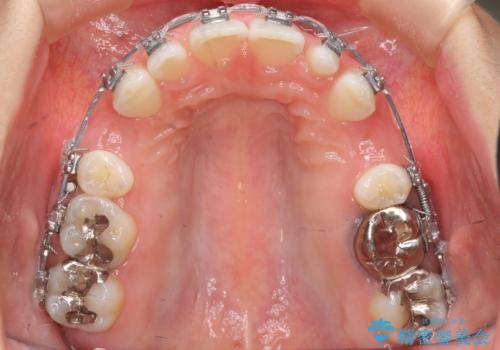

- 矯正装置

- メタル装置

- 出っ歯を主訴に来院。

かみ合わせが深く、治療に時間がかかりました。

上顎2番は矮小歯だったのをセラミックで被せています。